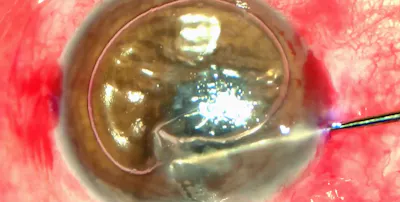

This patient was told nothing could be done about a nodular, keloid-type subepithelial scar.